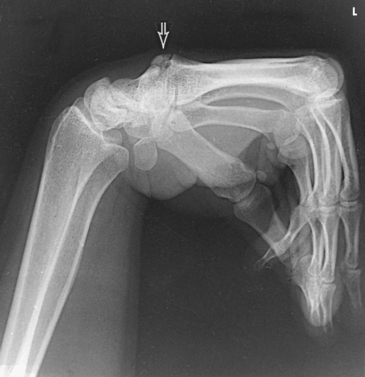

The elbow joint proper includes the proximal radioulnar articulation and the articulations between the humerus and the radius and ulna. The three joints are enclosed in a common capsule. The trochlea of the humerus articulates with the ulna at the trochlear notch. The capitulum of the humerus articulates with the flattened head of the radius. The humeroulnar and humeroradial articulations form a synovial hinge joint and allow only flexion and extension movement (Figs. 4-10 and 4-11, A). The proximal humerus and its articulations are described with the shoulder girdle in Chapter 5.

The three areas of fat1,2 associated with the elbow joint can be visualized only in the lateral projection (Fig. 4-11, B and C). The posterior fat pad covers the largest area and lies within the olecranon fossa of the posterior humerus. The superimposed coronoid and radial fat pads, which lie in the coronoid and radial fossae of the anterior humerus, form the anterior fat pad. The supinator fat pad is positioned anterior to and parallel with the anterior aspect of the proximal radius.

When the elbow is flexed 90 degrees for the lateral projection, only the anterior and supinator fat pads are visible, and the posterior fat pad is depressed within the olecranon fossa. The anterior fat pad resembles a teardrop, and the supinator fat pad appears as shown in Fig. 4-11, B. The fat pads become significant radiographically when an elbow injury causes effusion and displaces the fat pads or alters their shape. Visualization of the posterior fat pad is a reliable indicator of elbow pathology. Exposure factors designed to show soft tissues are extremely important on lateral elbow radiographs because visualization of the fat pads may be the only evidence of injury.